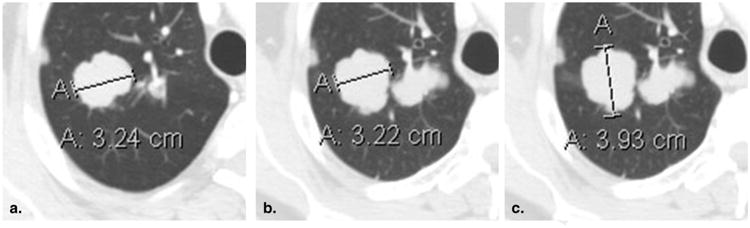

Figure 4.

Failure to change measurement axis with changes in lesion orientation (51-year-old male with metastatic adenoid cystic carcinoma of the tongue base). Baseline contrast-enhanced computed tomography of the chest viewed at lung window settings (a) demonstrates a mass in the right lung, correctly measured along its axis. At 8-week (time point #2) follow-up imaging (b), the original measurement axis was incorrectly maintained, resulting in the underestimation of true lesion size. Shifting the measurement to the new long axis (c) correctly captures the interval lesion growth.